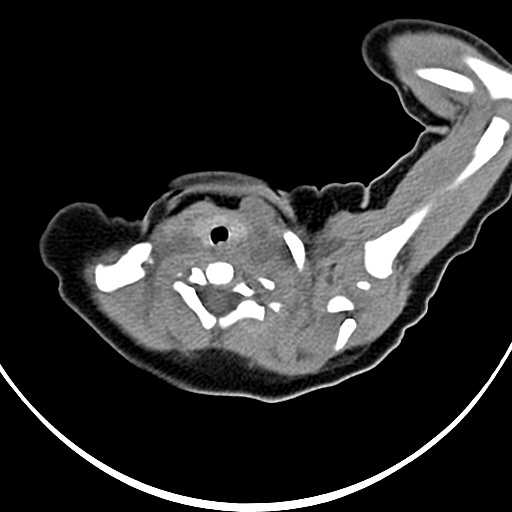

标题: PED1779:左侧锁骨下方异常密度影 请指教 [打印本页]

患者,男,1月,出生后一月,无明显诱因出现颈部左前方肿块。体检:左侧颈部轻度凸起包块,触之较硬。

病灶与左侧胸锁乳突肌分界不清,软组织密度,不似囊性改变,从病人的年龄及病变性状首先要除外先天性斜颈(肌性斜颈)可能。

左侧胸锁乳突肌肿大,考虑产伤所致

胸锁乳突肌挛缩(斜颈)?